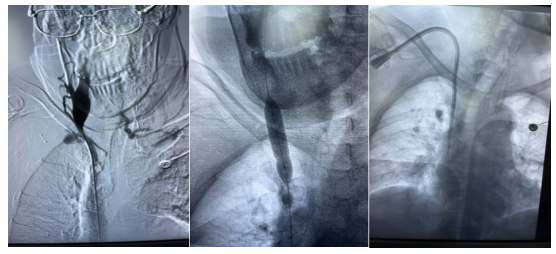

DSA影像

导管置入

会诊医生一致认为,建立稳定而有效的血管通路是长期血液透析的必须条件,也是血液透析患者的生命线,终末期肾衰竭患者长期血液透析首选的血管通路是动静脉内瘘,但本患者因长期的恶性高血压无法使用动静脉内瘘,患者带CUFF中心静脉长期导管置管是更好的选择。鉴于患者右侧锁骨下静脉狭窄,上腔静脉狭窄,无明显手术禁忌症,在征得患者及家属同意后,决定对患者行右侧上腔静脉造影术加上长期CUFF导管植入术(必要时血管成形术)。

下午15:00,肾病内科主治医师叶江、冯雪娇,介入医学科主任孙邱、主治医师陈江等人在介入科导管室为患者顺利完成了我院第一例在DSA下带CUFF中心静脉长期导管置入术。患者在手术过程中积极配合,术后情况良好,并连连感谢道:“真的太感谢你们了!你们技术这么好,以后透析时我一定给你们做宣传,让更多透析患者享受到这样好的技术。”